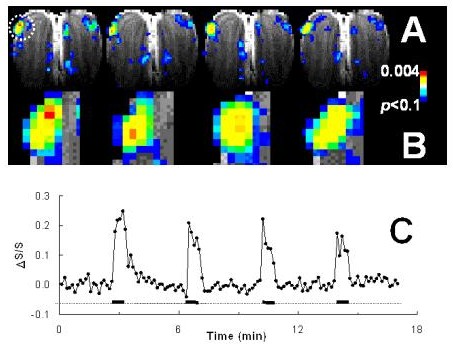

Stability of activity pattern in rat olfactory bulb. The pattern is in a coronal slice located in the middle region of te olfactory bulb. With 32-second exposures, the activity pattern is relatively stable.

520 ppm

32 seconds